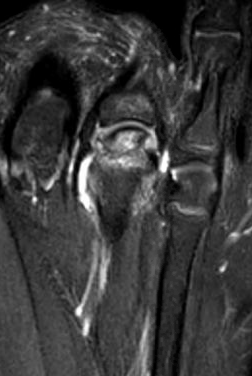

MRI